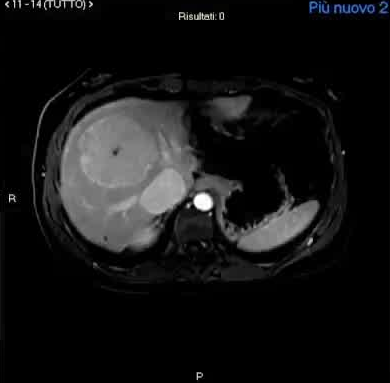

4. CE-MRI和CEUS是结节成像的首选方法。CE-MRI and CEUS are the preferred methods to image nodules.

- 使用肝胆造影剂的MRI对基线评估是必要的。MRI with hepatobiliary contrast agents is essential for baseline evaluation

- 使用细胞外造影剂的MRI可以进行纵向成像 Longitudinal imaging can be performed using MRI with extracellular contrast agents

CPSS-Nodule characterization